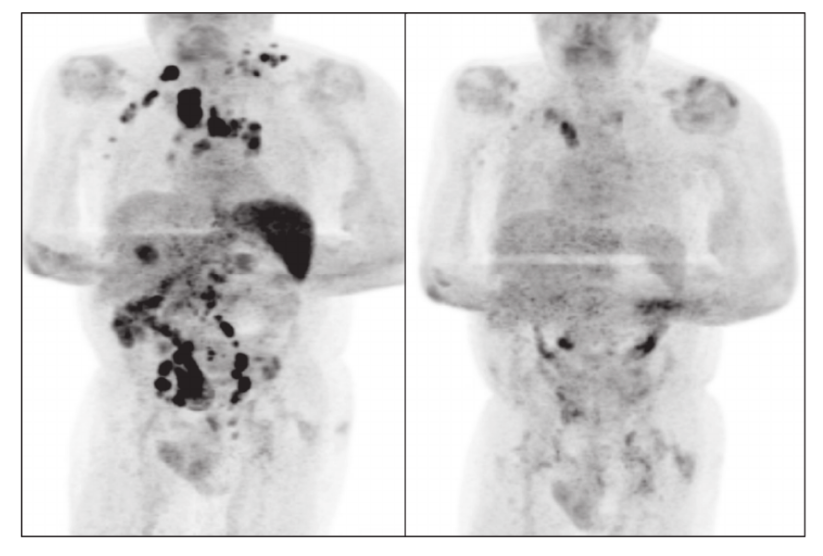

Sorpresivamente cuatro meses después, cuando le tocaba una revisión por el padecimiento de linfoma, los médicos notaron que la inflamación de los ganglios había reducido considerablemente y gracias a una exploración PET, una tomografía por emisión de positrones, se dieron cuenta que había una remisión generalizada del linfoma.